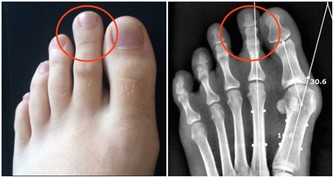

肚子凸起:

這是最簡單的判斷方法。臨床經驗顯示,90%以上的「大肚子」都是內臟肥胖者。

專家指出:男性腰圍>90釐米,女性腰圍>85釐米都是典型的「內臟脂肪型」肥胖。